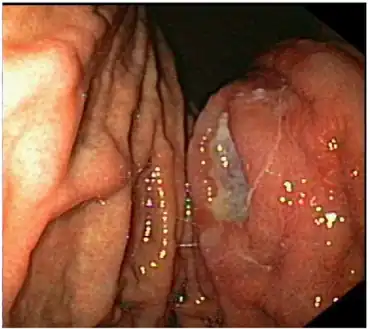

| Endoscopic image of gastric MALT lymphoma taken in body of stomach in patient who presented with upper GI hemorrhage. Appearance is similar to gastric ulcer with adherent blood clot. | |